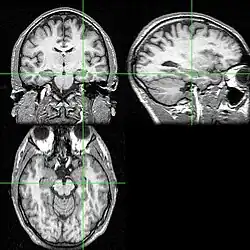

Recent research using neuro-imaging technology including PET and fMRI scanning has shown that there is an extensive amount of distributed brain activation during the process of episodic encoding and retrieval. Among the various regions, the two most active areas during the constructive processes are the medial temporal lobe (including the hippocampus) and the prefrontal cortex.[15] The Medial Temporal lobe is especially vital for encoding novel events in episodic networks, with the Hippocampus acting as one of the central locations that acts to both combine and later separate the various features of an event.[16][17] Most popular research holds that the Hippocampus becomes less important in long term memory functioning after more extensive consolidation of the distinct features present at the time of episode encoding has occurred. In this way long term episodic functioning moves away from the CA3 region of the Hippocampal formation into the neocortex, effectively freeing up the CA3 area for more initial processing.[17] Studies have also consistently linked the activity of the Prefrontal Cortex, especially that which occurs in the right hemisphere, to the process of retrieval.[18] The Prefrontal cortex appears to be utilized for executive functioning primarily for directing the focus of attention during retrieval processing, as well as for setting the appropriate criterion required to find the desired target memory.[15]